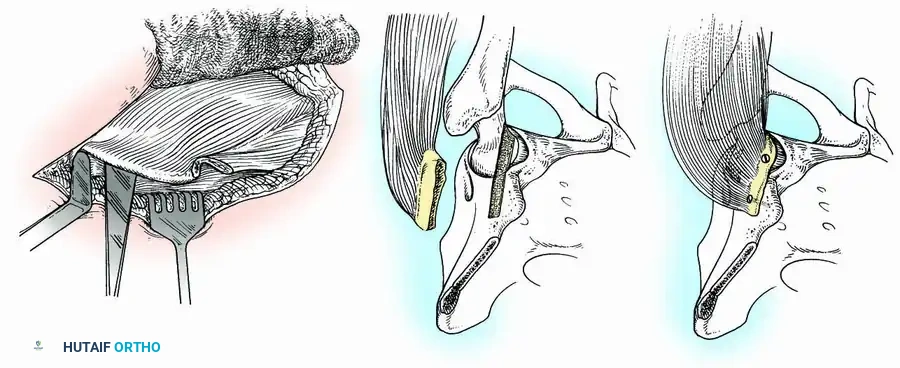

Surgical Technique 3-14:

* Incision: Begin an anterior iliofemoral incision 7.5 cm posterior to the anterior superior iliac spine (ASIS). Extend it along the anterior crest of the ilium to the ASIS, then curve it distally and posteriorly to end near the base of the greater trochanter.

* Exposure: Deepen the incision to the iliac crest. Identify the internervous plane between the sartorius and tensor fasciae latae. Detach the sartorius from its origin and retract it medially.

* Graft Harvest: By subperiosteal dissection, separate the abdominal aponeurosis and iliacus minor from the superior and medial ilium. Direct an osteotome longitudinally, then laterally, to cut a graft from the anterior crest. The graft remains attached to its muscle pedicle (tensor fasciae latae, anterior gluteus medius/minimus).

* Joint Preparation: Detach the straight head of the rectus femoris, open the capsule, and dislocate the joint. Perform a routine intra-articular denudation of cartilage. Reduce the hip.

* Slot Creation: Make a slot in the ilium above the acetabulum and in the anterior part of the head and neck of the femur to receive the graft.

Fig. 3-34: Arthrodesis of hip with muscle-pedicle bone graft. (A) Osteotome placement. (B) Slot creation in ilium and femoral head. (C) Graft fixed with screws.

- Fixation: Place the graft into the slot and secure it with screws (one in the ilium, one in the femoral neck). Alternatively, place the wide free surface of the graft on a flat bed prepared on the ilium and femur, fixing it with several pins.